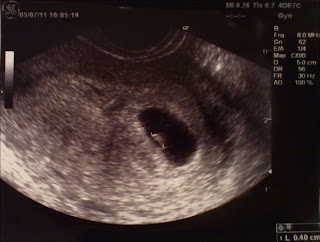

Eccolo lì! Sul monitor  c’è davvero un cuore che batte.. e com’è veloce!

La camera gestazionale non è più nera : dentro c’è un esserino di 4mm che pulsa pulsa e sta per ipnotizzarmi.